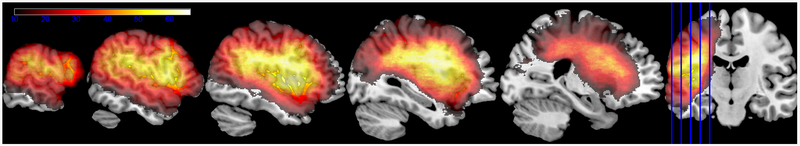

Lesion location was assessed based on MRI (n=68) or CT (n=55) brain scans, following the same procedures as previous studies of this data set (or sub-sets of these data). For the MRI scans, lesions were manually segmented on each participant’s T1-weighted structural image, then the structural scans and lesion maps were registered to the Montreal Neurological Institute (MNI) space Colin27 template by an automated process (Avants, Schoenemann, & Gee, 2006). For the CT scans, the lesion was drawn directly onto the Colin27 template after rotating it (pitch only) to match the approximate slice plane of the participant’s scan. Lesion coverage included the lateral portion of the left hemisphere exclusive of the occipital lobe and the medial and posterior inferior temporal lobe (Figure 1). Only voxels where at least 10 participants had lesions were included in the analysis (a total of 389,502 voxels) to provide a stable comparison of lesioned vs. non-lesioned performance. Both the coding of the naming data and the lesion drawing were done by individuals who were blind to the hypotheses tested here.

Figure 1.

Lesion overlap for the 123 participants (left hemisphere stroke) on the MNI space Colin27 template. The color scale ranges from 10 lesions (minimum for inclusion in analyses) to 66 (maximum observed overlap).